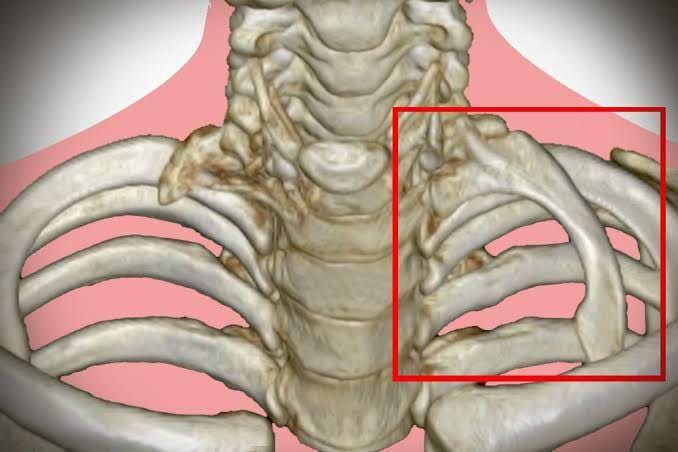

3. Beberapa orang punya tulang rusuk tambahan yang bisa menimbulkan masalah kesehatan

Hampir seluruh orang dewasa punya 24 tulang rusuk (12 pasang), tapi satu dari 500 orang punya tulang rusuk tambahan, disebut cervical rib. Tulang rusuk ini tumbuh di pangkal leher sedikit di atas tulang selangka. Namun, tulang rusuk tambahan ini biasanya tidak terbentuk sempurna, biasanya berupa jaringan tipis.

Di samping bentuknya tak wajar, tulang rusuk tambahan ini bisa menimbulkan masalah kesehatan jika letaknya berhimpitan dengan pembuluh darah. Hal itu memunculkan kondisi yang disebut thoracic outlet syndrome, menimbulkan rasa nyeri pada leher dan bahu, rasa lemas pada kaki, pembekuan darah, dan masalah lainnya.